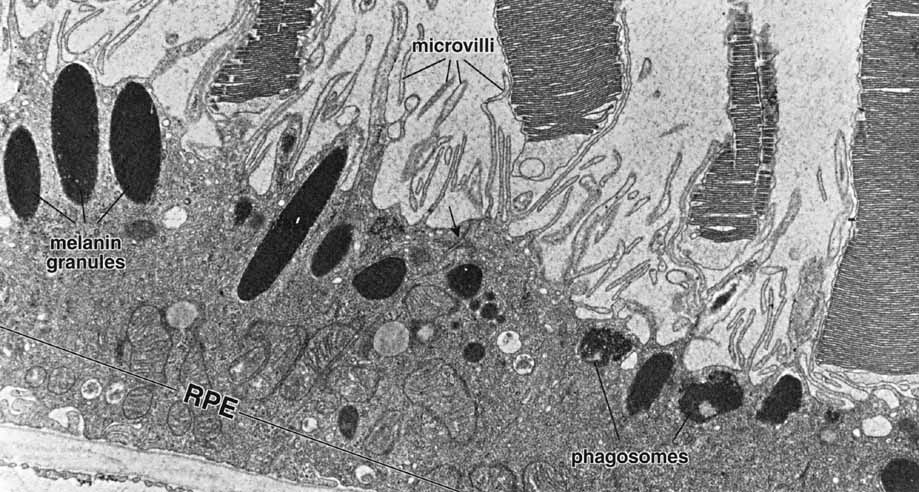

As already discussed, the topography of retinal development results in the intimate association of RPE apical microvilli with rod and cone photoreceptor outer segments across the intraretinal space (Figs. 4 and 6). These are bound together by the interphotoreceptor matrix (IPM), a network of proteins and proteoglycans containing a variety of enzymes, growth factors, carrier proteins, and other constituents.4 A number of constituents of this matrix have been localized in three distinct patterns, such as those that demonstrate rod- and cone-specific localization, those with an apical-to-basal heterogeneity, and others with a more homogeneous distribution. When there is a neurosensory retinal detachment, the potential interphotoreceptor space expands as fluid accumulates to form what is clinically referred to as the subretinal space, and the photoreceptors, now deprived of their supportive RPE functions, will degenerate if re-attachment is not effective. To maintain normal retinal attachment, RPE cells develop long slender apical microvilli of 5 to 7μm in length, forming sheaths that appear to participate in phagocytosis of outer segments. Villous processes surrounding rods contain smooth endoplasmic reticulum, ribosomes, melanin granules, and actin filaments. Villous processes that surround extrafoveal cones are usually devoid of intracellular organelles except for pigment granules. Despite their intimate relationship, no junctional attachments have been found between the RPE apical processes and the photoreceptor outer segments, although several molecular mechanisms forming the basis of this recognition and adhesion have been proposed, as discussed later.

Fig. 4 Electron micrograph of the retinal pigment epithelium in association with the outer segments of rods and cones. Retinal pigment epithelium (RPE) contains numerous elongated melanin granules that are aggregated in the apical portion of the cell, where the microvilli extend from the surface toward the outer segments of the rod and cone cells. The retina pigment epithelial cells contain numerous mitochondria and phagosomes. The arrow indicates the location of the junction complex between two adjacent cells, ×20,000. (Courtesy of Dr. Toichiro Kuwabara and reproduced from Ross et al. 2003)

RPE cells play a critical role in the process of turnover and renewal of shed photoreceptor outer segments (Figs. 14 and 15). The amount of material processed by the RPE is quite prodigious, and classic experiments identified both the diurnal nature of the process, and estimated that the total amount of photoreceptor membrane material processed per day may be as much as four times the surface area of the RPE cell membrane itself.55–57 The phagocytic process occurs through engulfment by the apical membrane of the RPE, and although the RPE is capable of slow, nonspecific phagocytosis of a diversity of large and small particles, it is the daily, specific phagocytosis of photoreceptor outer segment disks that constitutes one of the most important functions of RPE cells.58 If the phagocytic capacity of the RPE is impaired, the photoreceptor cells are unable to renew the outer segments, and as a consequence the photoreceptors degenerate and die. Once a phagosome has formed following internalization, fusion occurs with lysosomes, and if lysosomal proteases are inhibited, the RPE rapidly becomes engorged with undegraded phagosomes.59 The phagocytic load, that is, the number of photoreceptor disks shed per day per RPE cell, was calculated by Young to be 2000 disks per day in the parafovea, 3500 in the perifovea, and nearly 4000 in the periphery of the monkey eye. Phagocytosis by the RPE results in the complete turnover of the photoreceptor outer segments once every 8 to 13 days.60 Although the specific receptors of the apical RPE membrane involved in this process remain to be definitively identified, a variety of cell-surface proteins have been experimentally implicated in recognition, binding, and endocytosis of photoreceptor outer segments by RPE cells, including receptors for glycoproteins containing high levels of the sugar mannose,61 and cell surface receptors such as CD36 and the specific integrin alpha(v)beta5.62,63